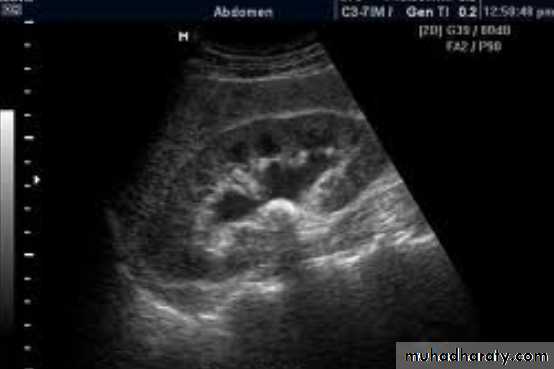

Doppler study of scrotal Swelling

Hematocele due to trauma treated conservative if small and by drainage if big examine the testis it could be injured also and may need open surgery.

Notice bruises of trauma